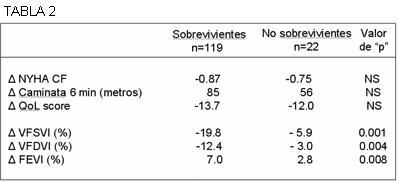

En la publicación de Bleeker y colaboradores (4), se analizan los resultados obtenidos en 101 pacientes que obtuvieron mejoría clínica, aunque solamente 73% de ellos se acompañaba de cambios ecocardiográficos correspondientes a un remodelado inverso. ¿Tiene esta divergencia valor pronóstico? En el gráfico modificado de Yu y colaboradores (9) (tabla 2), el interrogante es contestado; puede verse que las mejorías clínicas no aseguran mayor supervivencia, pues esta se haya invariablemente ligada al proceso de remodelado inverso.

Comentarios prácticos: en la tabla 2 es claro que el paciente puede ver mejorada su clase funcional, su evaluación de la calidad de vida y aun su capacidad para el ejercicio, sin que ello signifique una mayor probabilidad de supervivencia (tres parámetros superiores). En los tres parámetros inferiores se observan cambios significativos anatómicos y funcionales, que indican un positivo remodelado inverso del corazón y un incremento, con valor estadístico, de la supervivencia.

NYHA: New York Heart Association, QoL: score de Minnesota; VFSVI: volumen de fin de sístole ventricular izquierdo; VFDVI: volumen de fin de diástole ventricular izquierdo; FEVI: fracción de eyección ventricular izquierda.